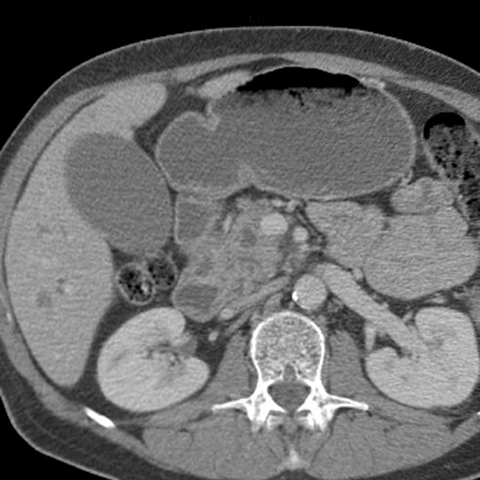

56 year-old male presents with painless jaundice [4 of 7]